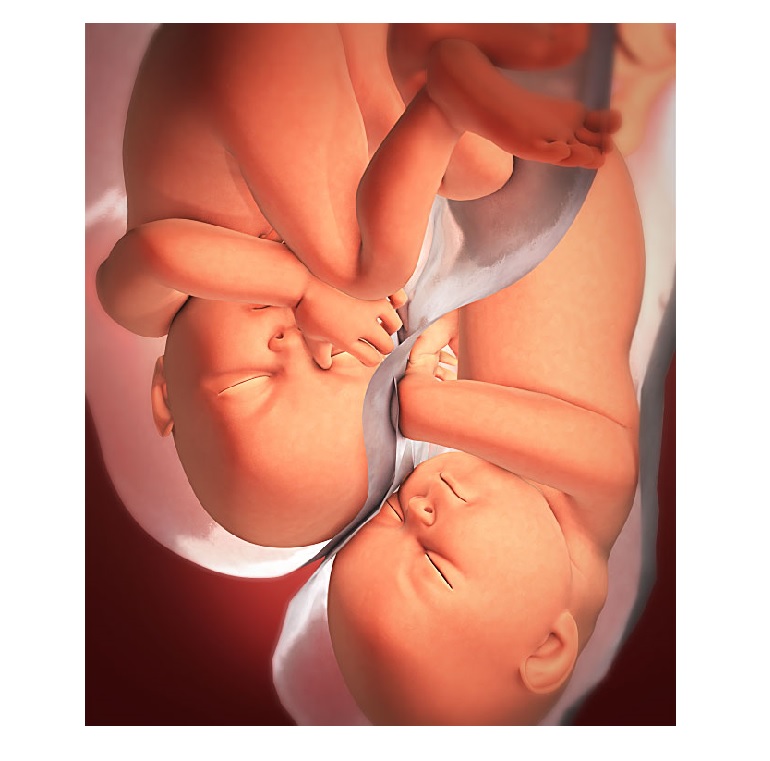

Успешное лечение бесплодия, а затем сохранение многоплодной беременности врачами КГБУЗ «КМКБ № 4».

Подробнее...